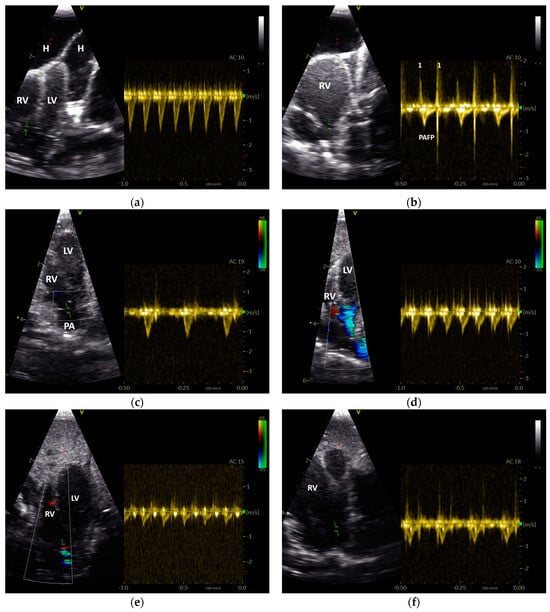

3.2. The Influence of Heart Failure on the Shape of the PAFP and AOFP

The investigations of the Doppler sonographic images of the diseased GPs revealed that the PAFPs were significantly different between the three groups (PAAP of group 1 to 2: p ≤ 0.05; group 1 to 3: p < 0.001; group 2 to 3: p = 0.004; Mann–Whitney U test). The longest PAAP was detected in cases without sonographic evidence of heart disease (group 1). Cases with an increasing involvement of the right heart in heart failure showed a significantly shorter PAAP and a longer PADP (group 1 to 2: p ≤ 0.05; group 1 to 3: p < 0.001; group 2 to 3: p = 0.009; Mann–Whitney U test). This could also be seen in group 2, with only cases with sonographic evidence of left heart failure showing a significantly shorter PAAP than cases without heart disease (group 1). These results are illustrated graphically in Figure 7. In contrast to the PAFP, the AOFP did not significantly vary between the different groups of diseased GPs (p > 0.05; Mann–Whitney U test; Figure 7).

Figure 7.

Comparison of the PW Doppler-derived acceleration phase (a) and deceleration phase (b) of the blood flow of the pulmonary artery and aorta of Congo grey parrots depending on the classification of their heart failure: group 1, cases without sonographic evidence of heart disease; group 2, cases with left heart failure; and group 3, cases with right or with left and right heart failure; The box plot shows the median (horizontal line in the centre), the 25th percentile (bottom box border), and the 75th percentile (top box border). The upper and lower ends of the whiskers show the maximum and minimum values. The single data points are outliers.

A systolic septal movement to the left could be seen in seven cases from group 3. In these cases, the PAAP (mean 31.8% ± SD 7.0) was shorter than the mean value of PAAP for the other cases in this group, but not significantly (p > 0.05; Mann–Whitney U test).